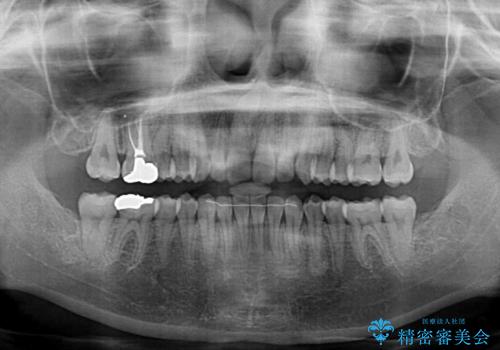

- 近々転勤の予定があるが、早めにインビザラインによる矯正治療を始めたいとのことで来院された患者様です。

上下ともにデコボコの程度は著しいものではなく、インビザラインで十分に対応可能な歯列不正でした。

後戻りによりスペースができてしまうことを避ける目的で、IPR(歯と歯の間を削る)を極力用いない矯正治療を行うこととしました。